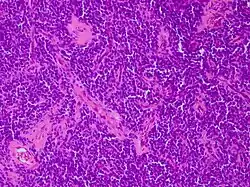

| Micrograph of an H&E stained section of a peripheral PNET. | |